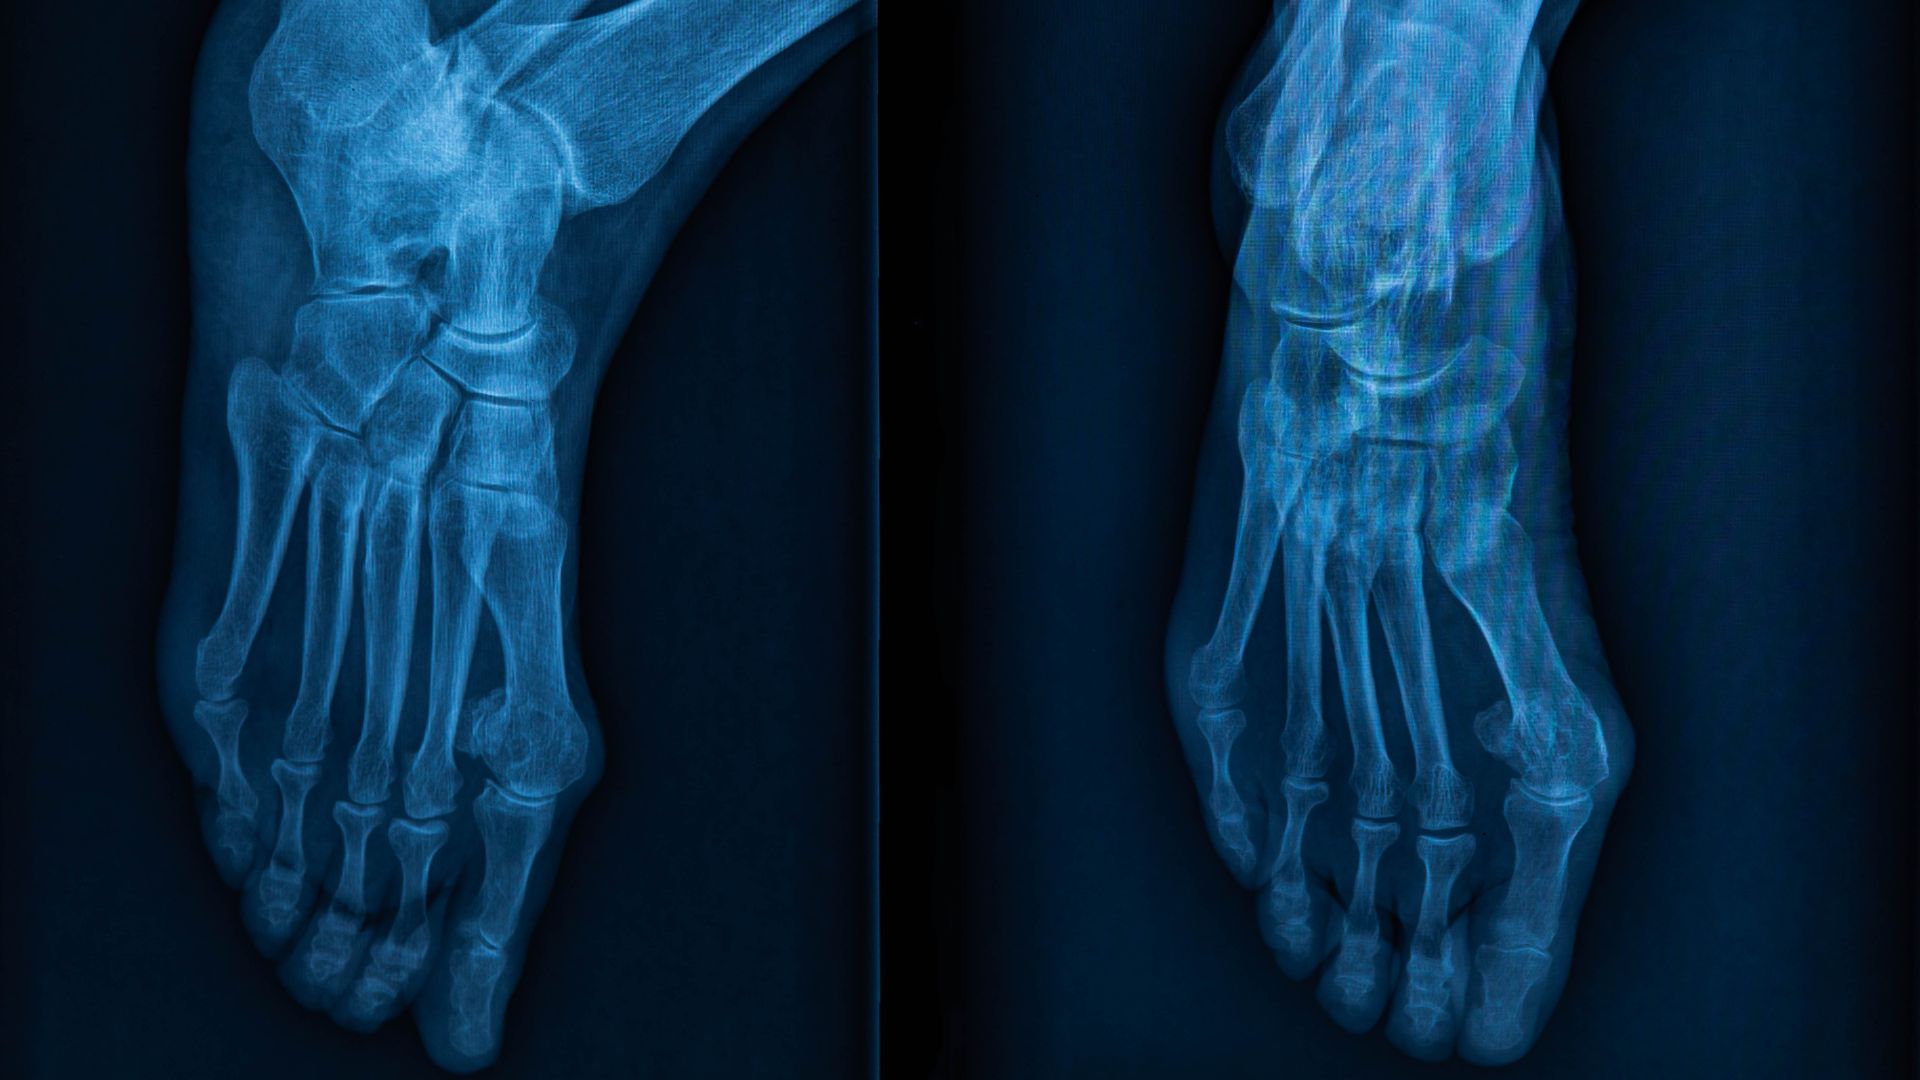

X-quang bàn chân là phương pháp sử dụng tia X để tạo hình ảnh các xương ở bàn chân, bao gồm xương cổ chân, xương bàn chân và các đốt ngón chân. Đây là kỹ thuật cơ bản, thường được chỉ định đầu tiên khi nghi ngờ tổn thương xương bàn chân. Phương pháp này không xâm lấn, thực hiện nhanh chóng và cung cấp hình ảnh rõ nét về cấu trúc xương.

Nguyên lý chụp X-quang bàn chân dựa trên việc tia X đi xuyên qua bàn chân và được hấp thụ khác nhau tùy theo mật độ mô. Xương hấp thụ tia X nhiều nên hiện lên màu trắng rõ nét trên phim, trong khi mô mềm hấp thụ ít hơn và hiện mờ hơn. Nhờ đó, bác sĩ có thể đánh giá hình dạng, vị trí, sự liên tục của các xương bàn chân cũng như các bất thường liên quan đến khớp.

- Chụp thẳng bàn chân (AP): Người bệnh nằm ngửa hoặc ngồi, bàn chân đặt sát phim, lòng bàn chân vuông góc với phim để quan sát tổng thể xương đốt bàn và ngón chân.

- Chụp nghiêng bàn chân (lateral): Bàn chân nghiêng, mặt bên sát phim để đánh giá chiều cao vòm bàn chân, vị trí gót và sự chồng lấp của các xương.

- Chụp chếch (oblique): Bàn chân nghiêng khoảng 45 độ giúp quan sát rõ các khớp bàn - ngón và các xương chồng lấp, giúp phát hiện tổn thương ẩn.